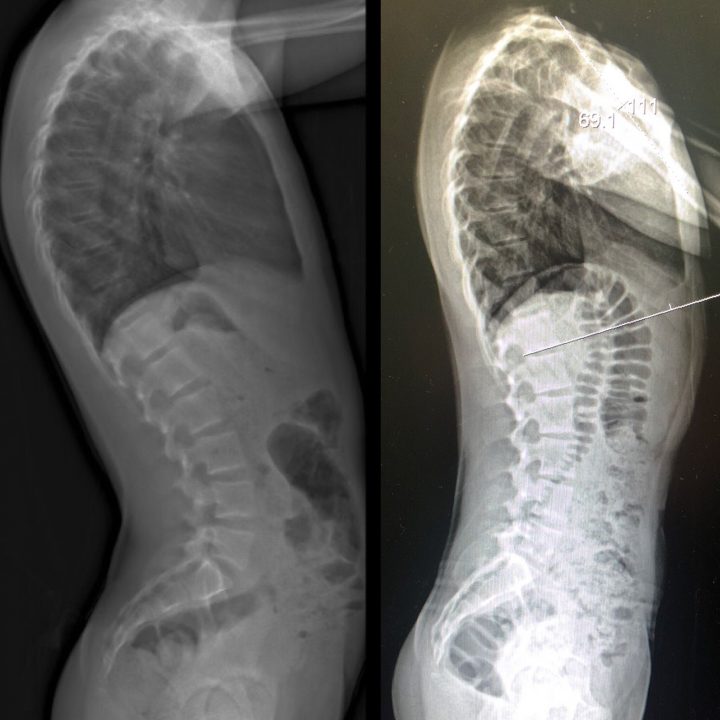

Plus, it was imperative that the teen actually comply with wearing his back brace in order to avoid major spinal surgery. Jackson was diagnosed in 2016 with an abnormally curved spine.

“Kyphosis is when the spine it’s almost like a hunchback,” Jackson’s mother Lauren said.

In order to treat this malformation of the spine which falls into the same family as scoliosis, Jackson underwent 3D imaging so the brace would be tailored to his body.